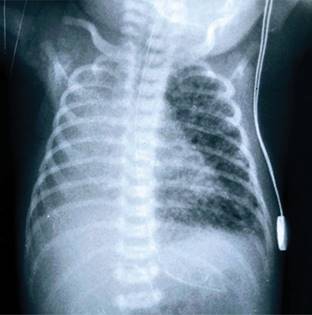

A las 32 h de vida nuevamente se detecta hipoxemia, aumento del trabajo respiratorio y acidosis respiratoria. En una nueva Rx de tórax se muestran imágenes de EPI en pulmón izquierdo (Figura 1), por lo que se decidió colocarla en posición decúbito lateral izquierdo y se disminuye la PMA hasta 8 cmH2O, mejorando la oxigenación.

Figura 1: Se observan imágenes radiotransparentes de forma redondeada localizadas en pulmón izquierdo, con hiperinsuflación pulmonar unilateral compatibles con enfisema pulmonar intersticial unilateral.